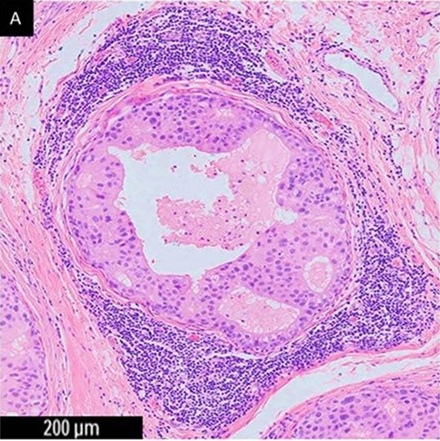

原因不明的肝門靜脈栓塞

(Portal vein thrombosis),抽血:凝血功能

PT、

APTT、

D-dimer、

Protein

C、

Protein S等都正常;不是自體免疫疾病;白血球正常,

CRP<0.1

mg/dL;電腦斷層只看到肝門靜脈栓塞

(沒有腫瘤

)。大部分的醫師會用抗凝劑治療,沒效後,沒轍了,一兩年後發生肝硬化。